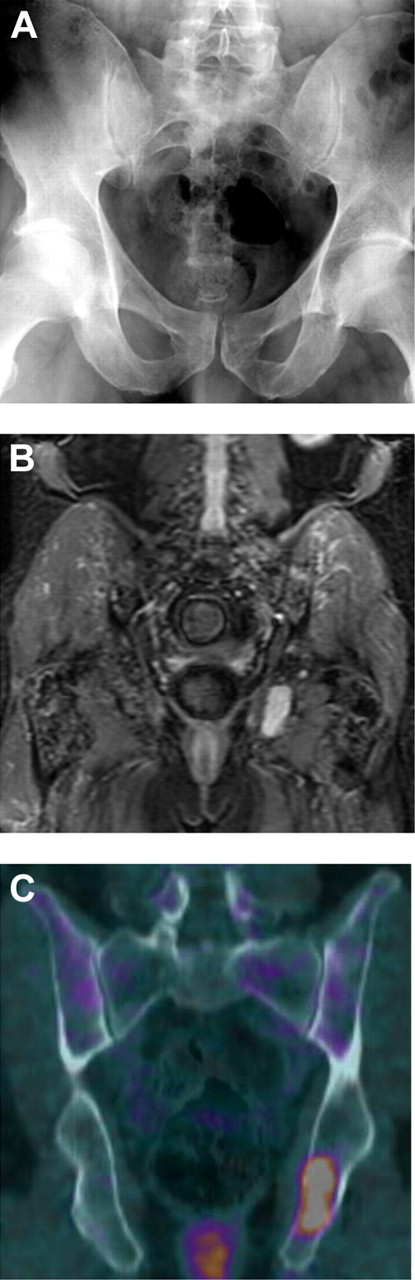

PET/CT is superior over conventional radiography. In the figure created by Bartel and colleagues, the conventional radiography of the pelvis (A) showed no osteolysis, while there were several foci on STIR-weighted MRI images with the largest in the left ischium (B), and 2 foci on FDG-PET/CT imaging (C) with the largest again in the left ischium with a max SUV of 4.1. See the complete figure in the article beginning on page 2068.

The first assessment of FDG-PET/CT in myeloma showed that this examination identified patients with high-risk myeloma, could be used to monitor nonsecretory myeloma, and could detect residual disease in patients with immunofixation negative complete response (CR).5 Larger studies of PET/CT in myeloma confirmed these data. Thus, PET/CT was included as an option for the diagnosis and monitoring of myeloma patients according to the National Comprehensive Cancer Network (NCCN) guidelines. The National Oncologic PET Registry, a large prospective program, enrolled 22 975 cancer patients, including more than 1300 patients with myeloma, and revealed that 36.5% of the time, treating physicians changed the intended management on the basis of PET/CT results.6 But is this justified for myeloma patients? The study by Bartel et al gives us important information for the use of FDG-PET/CT in myeloma patients treated with both novel agents and high-dose therapy. In 239 patients who underwent total therapy 3 (TT3), the authors performed standard skeletal survey, MRI, and FDG-PET/CT at baseline and then at specified points in their multiphased treatment. The presence of more than 3 focal lesions (FLs) in the PET/CT (PET-FL) independently predicted for inferior overall survival (OS) and event-free survival (EFS). Furthermore, complete FDG suppression in PET-FL before transplantation conferred superior OS and EFS. As in other studies, the presence of FLs in MRI and of lytic lesions in plain radiography (MBS-osteolytic lesions [OLs]) also predicted for shorter survival in the univariate analysis. However, the logistic regression analysis showed that although PET-FL was independently positively linked to both MRI-FLs and MBS-OL, only PET-FL retained its independent predictive value for survival, identifying a subset of patients with otherwise low-risk myeloma who had inferior survival. In addition, CR based on PET/CT criteria (absence of PET-FL and extramedullary disease) occurred more rapidly than the clinical CR or near CR and especially than the MRI-CR status among patients presenting with MRI-FL. Do these data indicate that PET/CT is superior to MRI in patients with myeloma? All reported studies to date have confirmed the superiority of PET/CT over conventional radiography (see figure).3 However, these studies have also revealed that if PET/CT was the sole imaging procedure, it would have missed additional small lytic skeletal lesions and diffuse spine involvement, which is readily detected by MRI.3,7 Another disadvantage of PET/CT is the false positive results especially in areas of inflammation or infection, deposits of brown fat, postsurgical changes, vertebroplasty changes, and occasionally other benign or malignant processes.8 In a prospective comparison among FDG-PET/CT, MRI, and conventional radiography, PET-CT was superior to plain radiographs, but, in 30% of patients, PET-CT scans of the spine and pelvis failed to show abnormal findings in areas in which MRI revealed an abnormal pattern of bone marrow involvement, more frequently of diffuse type. In contrast, in 35% of patients, PET-CT enabled the detection of myelomatous lesions in areas that were outside the field of MRI. By combining MRI of the spine-pelvis and PET-CT, the ability to detect sites of active multiple myeloma (MM), both medullary and extramedullary, was as high as 92%. After autologous stem cell transplantation, 15 of 23 patients had negative PET-CT scans (including 13 with very good partial response or near CR), while only 8 had normal MRI.9